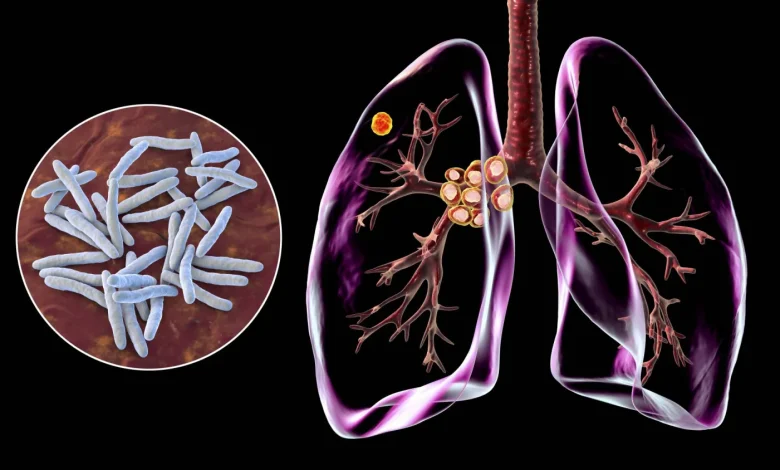

في خطوة علمية متقدمة كشفت دراسة حديثة من إسبانيا عن أسلوب مبتكر لفهم انتشار مرض السل، وذلك من خلال استخدام تقنيات التسلسل الجيني لرصد حركة العدوى بدقة غير مسبوقة.

وبمناسبة اليوم العالمي للسل تسلط هذه الدراسة الضوء على الدور المتنامي لتحليل الحمض النووي «دي إن إيه» في كشف سلاسل انتقال خفية للمرض، وتوجيه التدخلات الصحية بشكل أكثر فاعلية. ففي إقليم كاتالونيا يتم تشخيص أكثر من 1200 حالة سل سنوياً، لكن يبقى التساؤل قائماً: كم عدد الحالات التي تمر دون اكتشاف؟ وكيف تنتقل البكتيريا فعلياً داخل المجتمعات؟

بصمة وراثية لكل حالة

تعتمد طرق تتبع السل التقليدية على تتبع المخالطين، أي سؤال المرضى المصابين عن الأشخاص الذين قضوا وقتاً معهم، ثم فحص هؤلاء الأفراد. لكن هذه الطريقة بها نقاط عمياء. فقد لا يعرف الأشخاص أنهم تعرضوا للعدوى، أو قد لا يتذكرون كل تفاعل.

ويقدم التسلسل الجيني عدسة مختلفة، فمن خلال تحليل المادة الوراثية لبكتيريا المتفطرة السلية Mycobacterium tuberculosis المسببة للمرض من كل مريض يمكن للعلماء مقارنة السلالات. فإذا كان مريضان يحملان جينومات بكتيرية متطابقة تقريباً ولا تفصل بينهما سوى بضع طفرات، فمن المرجح جداً أنهما جزء من نفس سلسلة الانتقال.

السلالة المهيمنة والارتباط بالوافدين

كما حللت الدراسة السلالات البكتيرية التي جُمعت من جميع أنحاء كاتالونيا بين ديسمبر (كانون الأول) 2021 ويونيو (حزيران) 2023. وتظهر النتائج أن السلالة الأكثر شيوعاً، والتي تسمى «إل4» L4 توجد في كل مكان في الإقليم، سواء بين السكان الأصليين، أو بين المقيمين من المولودين خارج إسبانيا.

لكن السلالات الأخرى تروي قصة أكثر تحديداً، حيث تظهر سلالات مثل L1/EAI وL2/Beijing وL3/CAS بشكل متكرر في مناطق جغرافية معينة، وغالباً ما ترتبط بأشخاص يتحدرون من أجزاء من العالم تنتشر فيها هذه الأنواع الفرعية.

وعلى سبيل المثال فإن سلالة بكين (L2) شائعة في شرق آسيا، بينما سلالة CAS (L3) أكثر شيوعاً في وسط وجنوب آسيا.

«قاتل عالمي» لا يزال بيننا

غالباً ما يُعتقد أن السل مرض من الماضي. لكن الأرقام تقول غير ذلك. فعلى الصعيد العالمي، يصاب أكثر من 10 ملايين شخص بالسل كل عام، ويموت نحو مليون ونصف بسبب المرض. ففي عام 2023 استعاد السل موقعه كأول سبب للوفاة من عامل معدٍ واحد على مستوى العالم متجاوزاً كوفيد-19.